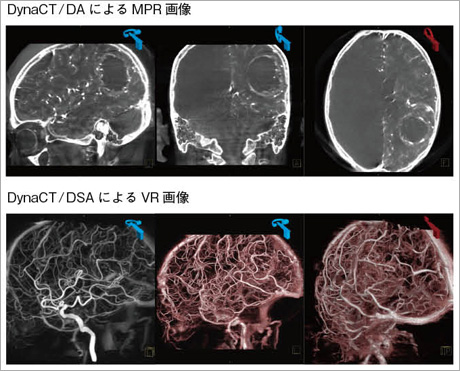

図1 塞栓術後(PVA form)のmeningioma

図2 脳腫瘍(造影)